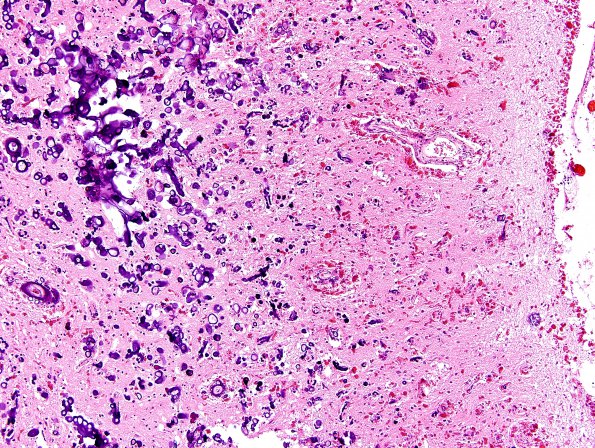

Some areas, such as this portion of the hippocampus, show focal calcifications with admixed Rosenthal material (H&E).